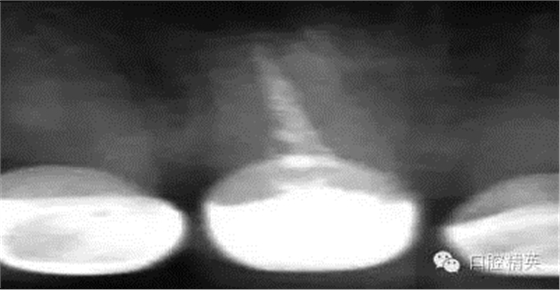

根管治療更是牙體修復(fù)的基礎(chǔ),根據(jù)術(shù)前診斷,對(duì)需要做根管治療的或有必要重新做根管治療的,一定要做到恰充,消除隱患,避免將來(lái)冠修復(fù)好后,出現(xiàn)根尖炎癥的問(wèn)題(見(jiàn)圖3、4、5)。在基礎(chǔ)工作做好后,接下來(lái)開(kāi)始牙體預(yù)備,根據(jù)跟個(gè)人習(xí)慣,選擇合適的車針(圖6、7)。